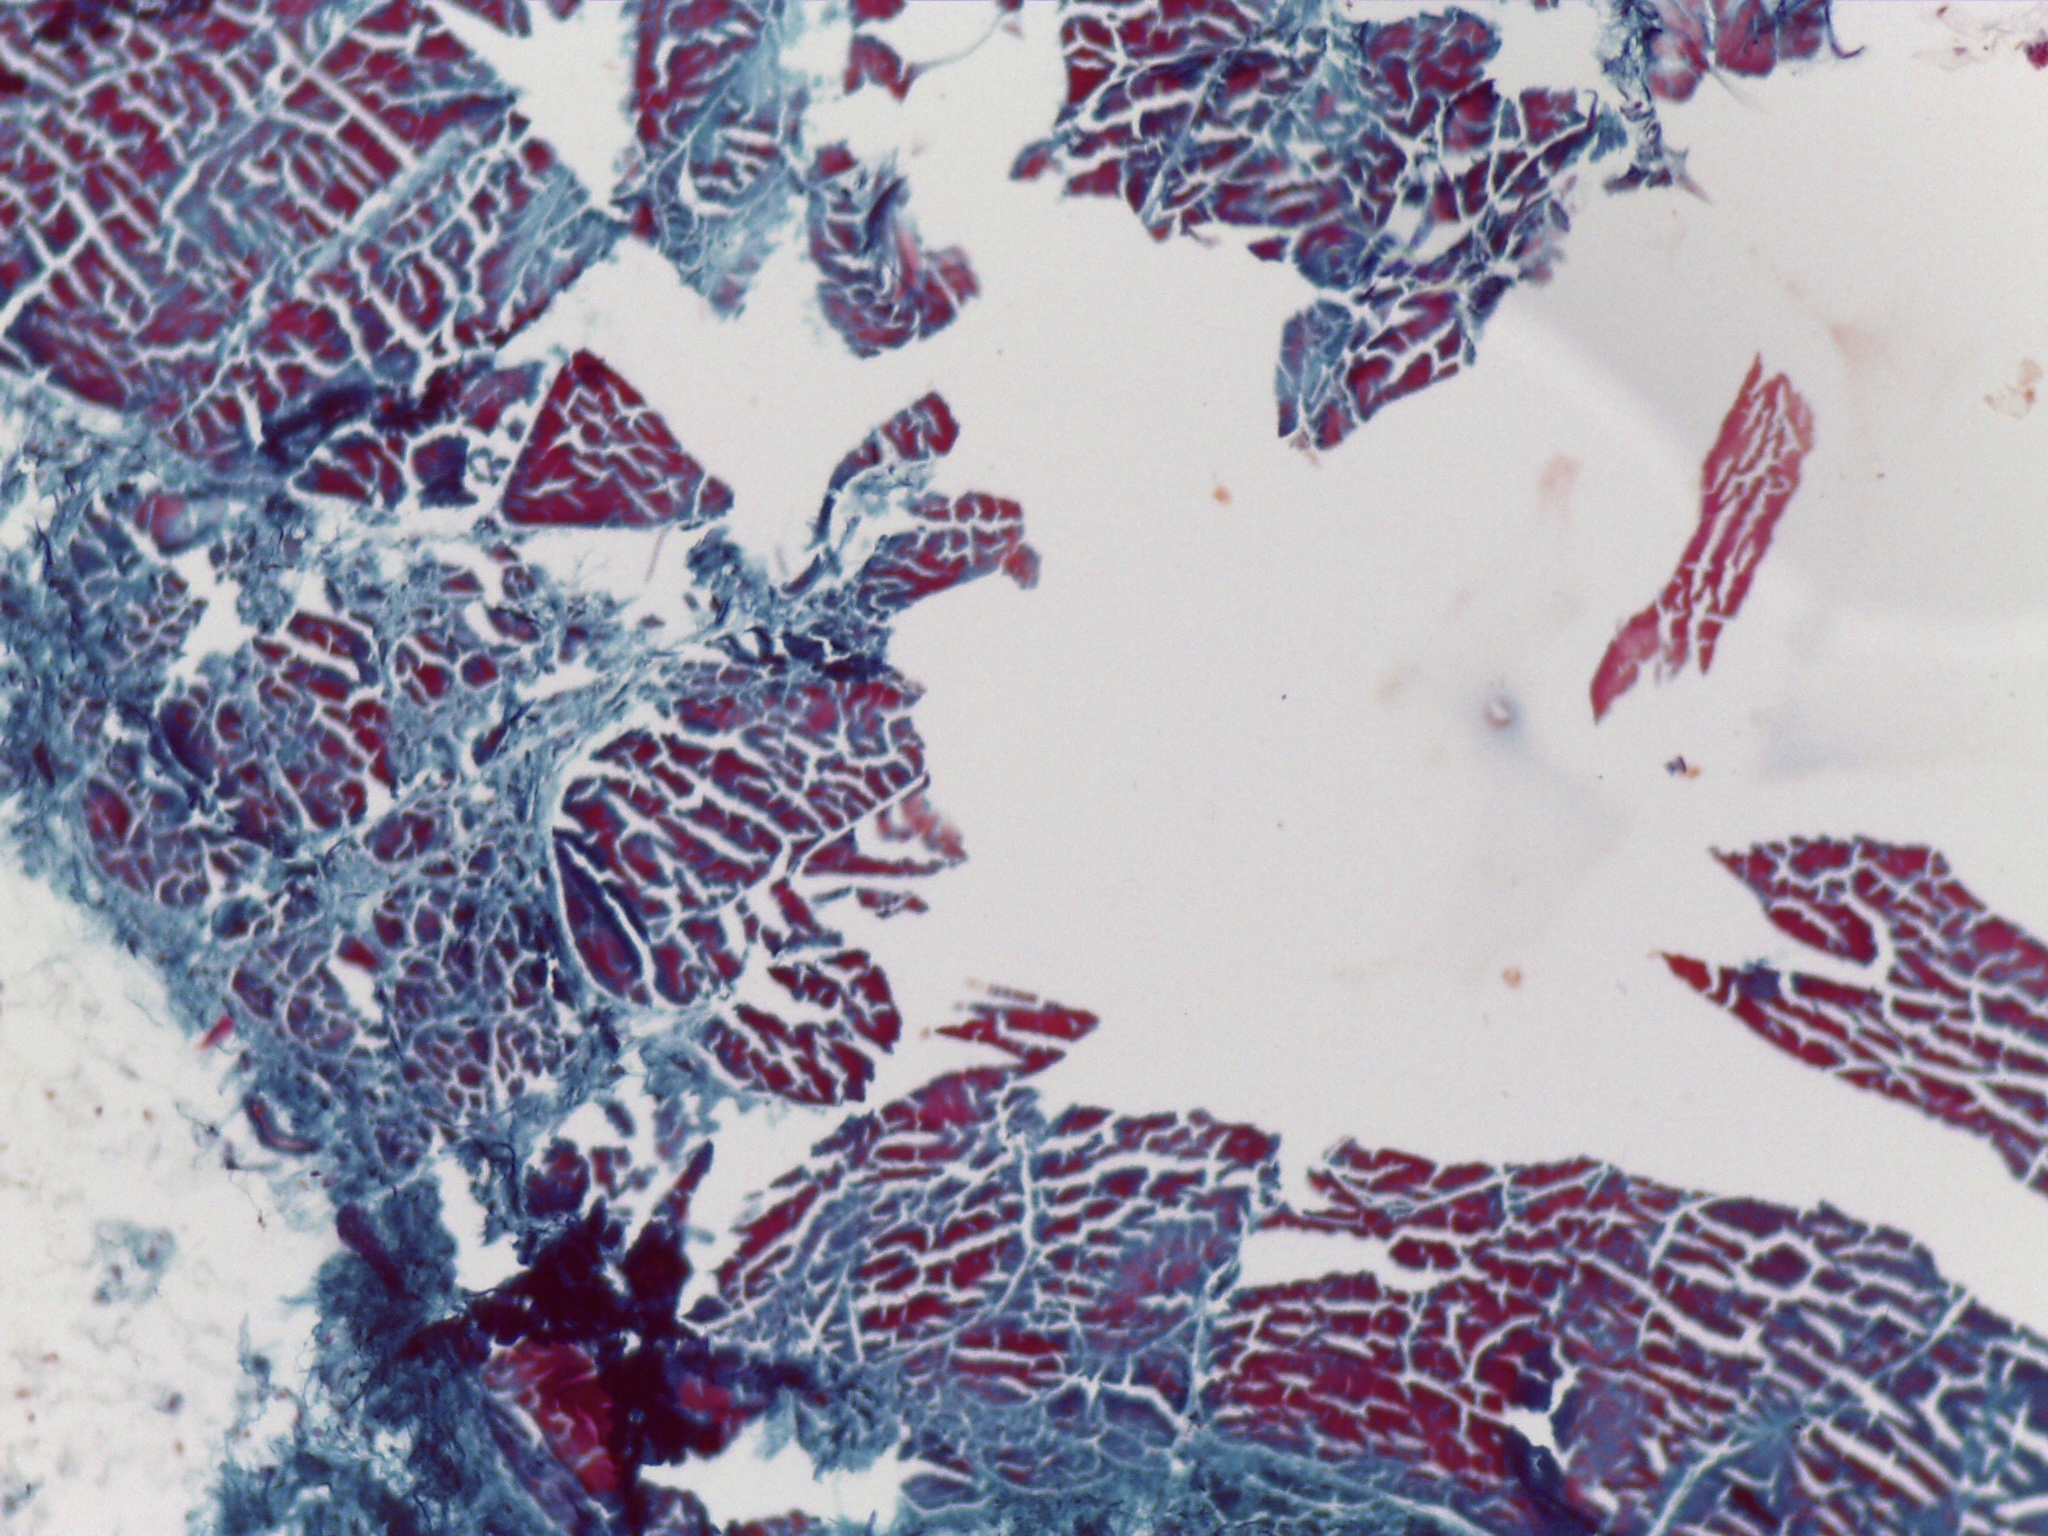

During my four years at university I have found myself being heavily influenced by science and biology, both of humans and plants, but more specifically on the skin and how much visual information can be contained within a single cell. I have been focusing my research on the skin condition vitiligo and the unusual patterns it creates on the body; I’ve always been confused and interested by the random patches so I began an exploration into how skin cells work and how this condition can be triggered. Through this I met some amazing scientists who inspired me through microscope imagery of the skin and lab experiments on the skin. I saw pinks, purples and blues, organic and uncontrolled structures contained within perfect shapes, and patterns hidden to the naked eye.

The imagery that I have gathered of these microscope images and of vitiligo patches has greatly inspired my work, as I have used similar colours and patterns and I have used techniques to try capture the randomness whilst making it controlled and perfected. Below are some of my own imagery that I have taken and some of my own paintings.